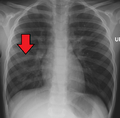

| Chest X-ray of a pneumonia caused by influenza and Haemophilus influenzae, with patchy consolidations, mainly in the right upper lobe (arrow) | |

A chest radiograph is frequently used in diagnosis.[23] In people with mild disease, imaging is needed only in those with potential complications, those not having improved with treatment, or those in which the cause is uncertain.[23][67] If a person is sufficiently sick to require hospitalization, a chest radiograph is recommended.[67] Findings do not always match the severity of disease and do not reliably separate between bacterial and viral infection.[23]

X-ray presentations of pneumonia may be classified as lobar pneumonia, bronchopneumonia, lobular pneumonia, and interstitial pneumonia.[73] Bacterial, community-acquired pneumonia classically show lung consolidation of one lung segmental lobe, which is known as lobar pneumonia.[41] However, findings may vary, and other patterns are common in other types of pneumonia.[41] Aspiration pneumonia may present with bilateral opacities primarily in the bases of the lungs and on the right side.[41] Radiographs of viral pneumonia may appear normal, appear hyper-inflated, have bilateral patchy areas, or present similar to bacterial pneumonia with lobar consolidation.[41] Radiologic findings may not be present in the early stages of the disease, especially in the presence of dehydration, or may be difficult to interpret in the obese or those with a history of lung disease.[24] Complications such as pleural effusion may also be found on chest radiographs. Laterolateral chest radiographs can increase the diagnostic accuracy of lung consolidation and pleural effusion.[40]

Right middle lobe pneumonia in a child as seen on plain X-ray